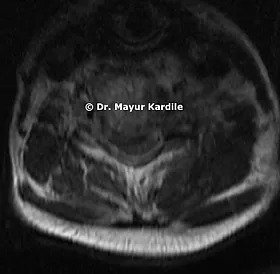

Her MRI revealed infection at C5 and C6 vertebral level with kyphosis

The infective tissue was pressing on the spinal cord giving rise to symptoms of cervical myelopathy